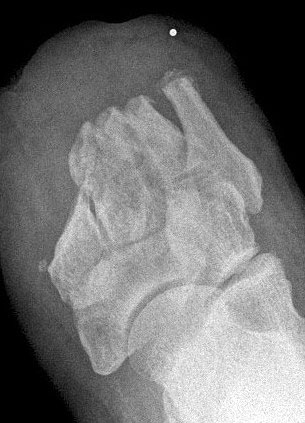

Fehler in der Amputationstechnik

• Die Knochenenden müssen so gestaltet und gedeckt werden, dass die umgebenden Weichteile nicht geschädigt werden. Z. B. können nach transmetatarsaler Amputation überstehende Mittelfußknochen die Haut perforieren (Abb. 9, 10).

• Wurde ein Sehnensansatz entfernt, müssen die funktionellen Auswirkungen bzw. die Fehlstellungen berücksichtigt und das Muskelungleichgewicht durch geeignete Maßnahmen korrigiert werden. Es müssen Equinus-, Valgus- oder Varusstellungen vermieden werden. Das gilt speziell für die Lisfranc- und Chopartamputation, die bei falscher Technik durch Zug des Trizeps surae mit einer Spitzfußstellung einhergeht (Abb. 11).

• Ein spannungsfreier Wundverschluss ist essentiell. Deshalb sind im Hinblick auf den Wundverschluss ausreichend Weichteile zu belassen bzw. genügend Knochen zu resezieren. Bei zu großer Spannung an den Wundrändern resultiert eine Wunddehiszenz (Abb. 12).